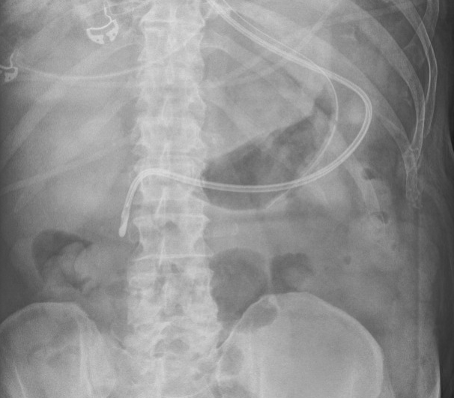

The Technique (continued)

6) Obtain abdominal xray to verify placement (and perhaps CXR as well to exclude PTX)

(Here we see tip of tube in second portion of duodenum)

7) Remove stylet, ok to use